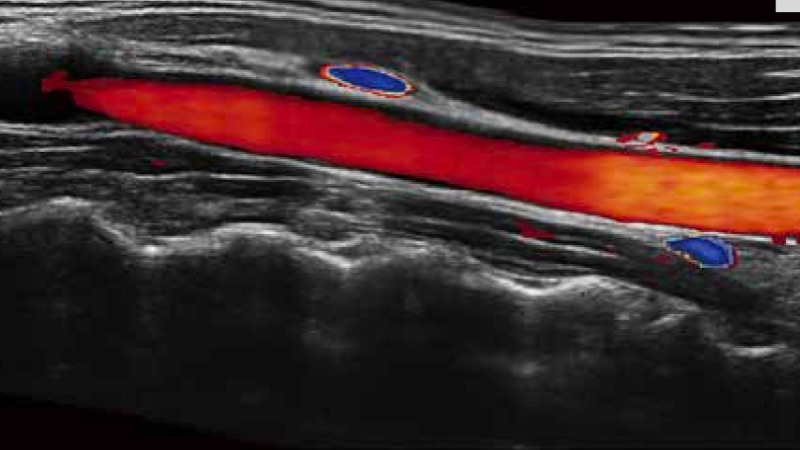

实时宽景成像技术

通过彩色血流和实时宽景相结合,可观察到完整的动静脉血流,方便医生检查。实时扫查过程中,如有任何操作失误也可以很容易地进行回扫擦除,而不会中断扫查。

临床图像